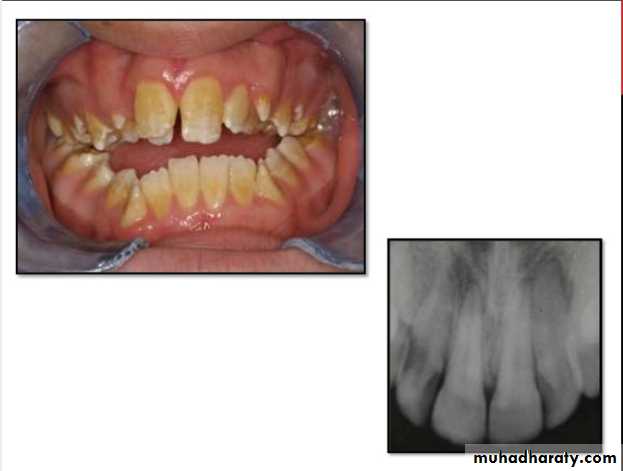

• Dentinogenesis Imperfecta: Is an inherited disorder of dentin formation due to autosomal dominant disturbance.

Affects both primary&permanent dentition.

Blue to brown discoloration with distinctive translucence.

Enamel frequently separates easily from underlying defective dentin.

Dentinogenesis Imperfecta(Hereditary Opalascent Dentin)

Radiographically:

Bulbous crownsCervical constriction

Thin roots

Early obliteration of roots canals & pulp chambers.

Treatment:

Prevent loss of enamel& subsequent loss of dentinthrough attrition.

Cast metal crowns for posterior & jacket crowns for anterior teeth